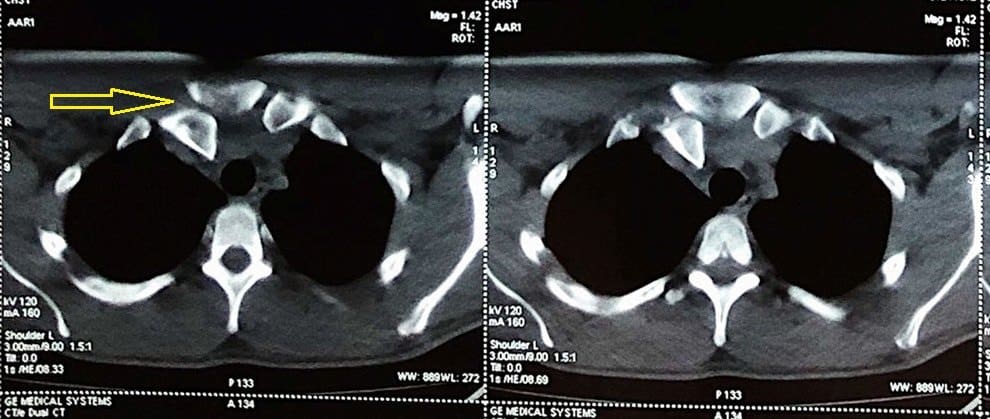

Trật khớp ức đòn

» Thông tin: Nam giới – 23 tuổi.

» Lâm sàng: Chấn thương vai phải.

# Trật khớp ức-đòn phải ra sau.